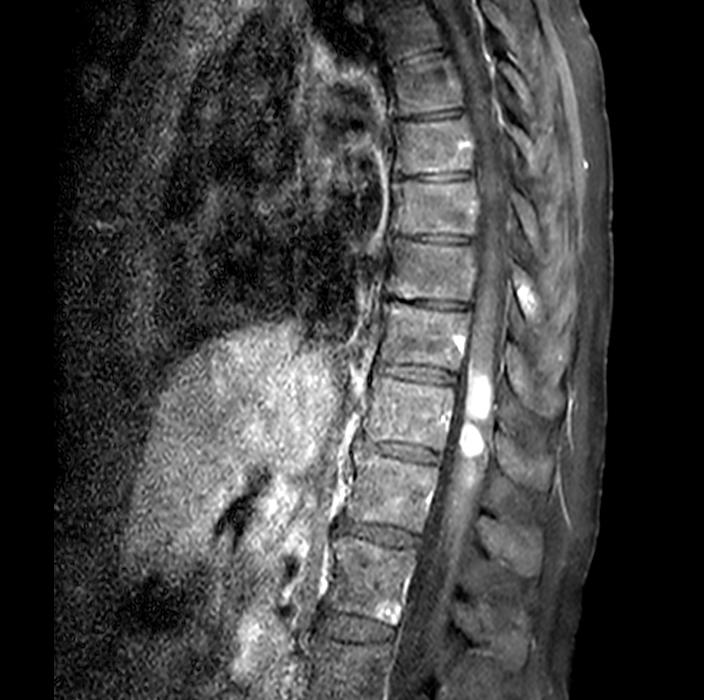

ziente accedeva in Pronto Soccorso, ove una risonanza magnetica dell’encefalo riscontrava multiple lesioni secondarie cerebrali. La paziente veniva quindi sottoposta a radioterapia panencefalica. Si avviava trattamento eziologico sistemico con trastuzumabemtansine (TDM-1), proseguito da Novembre 2020 per 28 mesi, ottenendo stabilità di malattia e buona tolleranza (episodica piastrinopenia G1). A Maggio 2024 la paziente lamentava ricomparsa di instabilità della marcia ed ipostenia degli arti superiori e inferiori, evolutisi nell’arco di 72 ore in completa impossibilità alla deambulazione, alla quale si associavano incontinenza urinaria e fecale. Recatasi in Pronto Soccorso, la

paziente veniva sottoposta a tomografia assiale computerizzata (TC) dell’encefalo, non dimostrativa, e a RM encefalo e rachide, la quale deponeva per disseminazione liquorale olo-cordica di neoplasia nota in anamnesi e multiple localizzazioni intraventricolari. Previa discussione multidisciplinare, si avviava trattamento di seconda linea con trastuzumab deruxtecan 5,4 mg/kg endovena ogni 21 giorni. La prima rivalutazione radiologica (20/08/2024) ha evidenziato la pressoché completa regressione delle lesioni ripetitive intra-midollari ed intraventricolari precedentemente descritte (figure 1 e 2). Permanevano riconoscibili unicamente due piccole lesioni focali all’altezza del passaggio T2-T3 e del passaggio T7-8, entrambe in riduzione dimensionale. Attualmente la paziente sta proseguendo il trattamento, con beneficio clinico ed iniziale ripresa della mobilità.